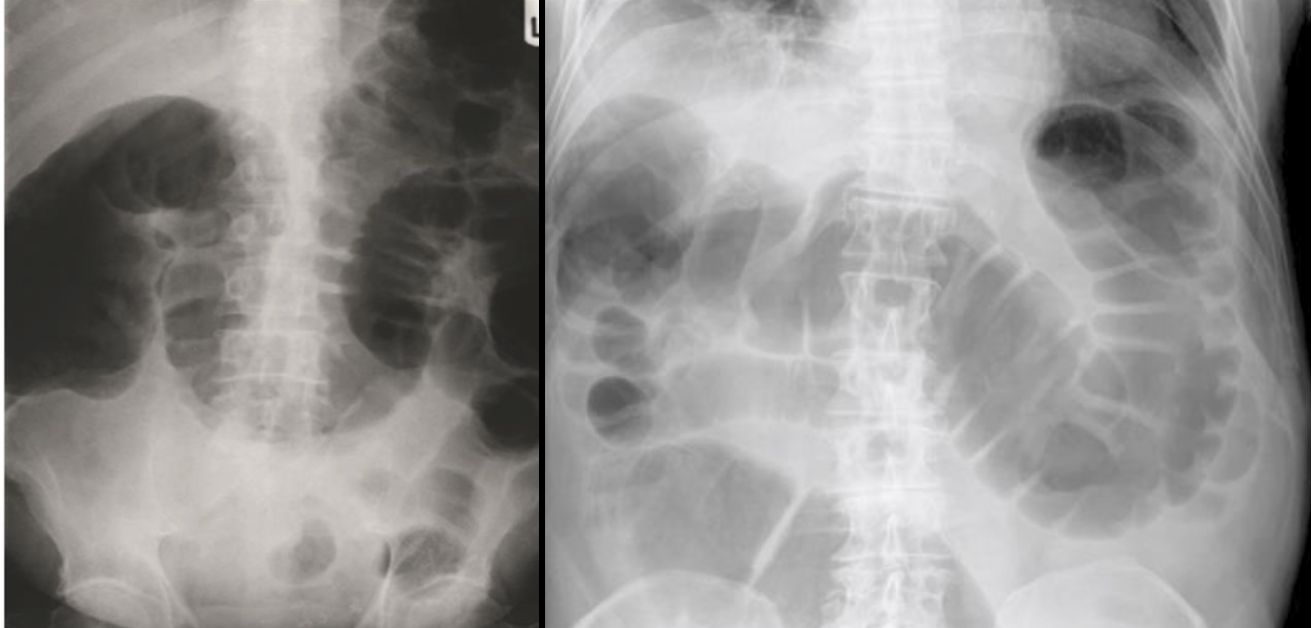

Radiology Imaging

- Plain radiography (flat and upright)